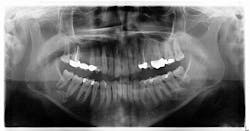

Radiographic assessment revealed a radiopaque s-/oval-shaped lesion on the right side of the mandible just inferior to the apical roots of tooth no. 31 (figure 1). The patient reported no sensitivities or tenderness in the area and was unaware of any potential pathology. Previous panoramic radiographs were not obtainable. At that time, we explained to the patient that we would reexamine the lesion with a subsequent radiograph in the next year to assess for any changes.